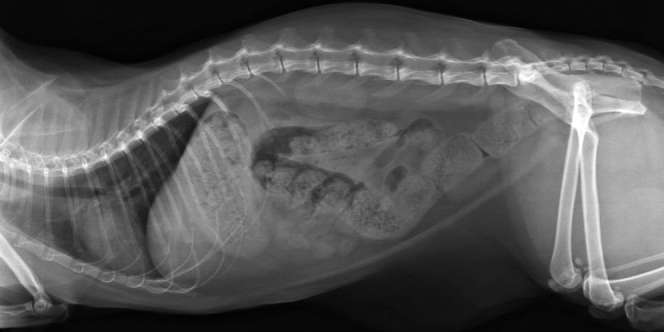

Dream - Sebanyak 200 paku ditemukan bersarang di dalam perut bocah berusia 15 tahun asal Ji'an, Provinsi Jiangxi, China. Logam-logam tersebut diduga dimakan bocah yang tak disebutkan namanya itu dalam rentang waktu sebulan.

Keberadaan paku-paku ini diketahui setelah bocah lelaki itu mengeluh sakit perut. Keluhan itu disampaikan kepada orangtuanya pada 6 Juni 2016. Mendapat keluhan itu, semula orangtuanya menganggap anaknya itu hanya sakit perut biasa.

Namun, karena tak ingin terjadi apa-apa, bocah tersebut dibawa ke rumah sakit. Doktermemeriksanya. Untuk memastikan penyakit apa yang diderita, bocah itu menjalani CT scan.

Dan betapa terkejutnya para dokter yang menangani bocah ini. Sebab, mereka melihat benda aneh di dalam perut bocah ini. Hasil CT scan menunjukkan tumpukan paku bersarang di lambung.

Operasi pun segera dilakukan. Sebanyak 200 paku berhasil dikeluarkan. Tak hanya paku, ditemukan pula tusuk gigi, batu, dan koin. Semua benda itu beratnya hampir 7 kilogram.

Setelah operasi itu sang bocah mengaku telah memakan benda-benda itu selama sebulan belakangan. Kepada wartawan, orangtua bocah ini mengaku tak tahu kenapa anaknya melakukan perbuatan tak lazim ini.

Menurut para dokter, bocah ini mengalami Pika, kelainan di mana seseorang cenderung memakan benda-benda asing seperti batu, besi, dan kaca. Kasus seperti ini bukanlah kasus pertama di dunia. (Sumber: Daily Mail)